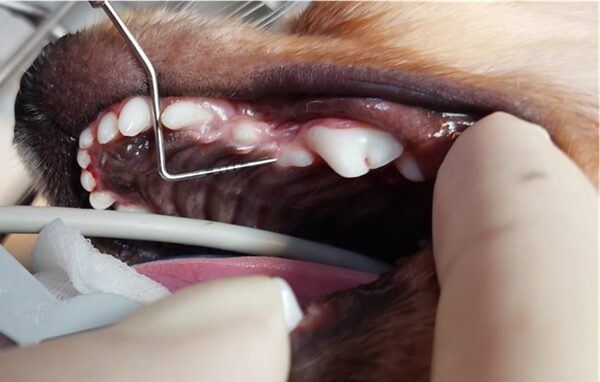

Bei Rex, einem 12 jährigen Mischlingsrüden, fiel starker Mundgeruch auf. Dies ist immer ein Warnsignal, da Tiere Beschwerden mit den Zähnen nicht kommunizieren können. Das Ausmaß des Mundgeruchs korreliert dabei meist mit dem Schweregrad der Zahnerkrankung. Keinesfalls sollte man annemen, dass Mundgeruch bei älteren Tieren normal und unproblematisch ist.

Sein Gebiss wies sehr viel Zahnstein auf und auch eine ausgeprägte Zahnfleischentzündung.

Das wahre Ausmaß zeigte sich allerdings erst nach ausführlicher Untersuchung in Narkose. Das Dentalröntgen und die Sondierung zeigten, dass bereits große Teile des Kieferknochens durch die Parodontitis verursachenden Bakterien zerstört wurde (die gelbe Linie zeigt an, wo der Kieferknochen sien sollte, die rote zeigt an wieviel Knochen bereits zerstört wurde). Dieser Knochenschwund ist leider irreversibel und in diesem Endstadium hilft nur noch die Extraktion.

Parodontitis ist aber nicht nur eine lokale Erkrankung, die zu Schmerzen, Abszessen und Kieferbrüchen führen kann, sondern betrifft den gesamten Körper, da die Bakterien durch das entzündete Zahnfleisch in die Blutbahn übergehen und dadurch in den gesamten Körper streuen.